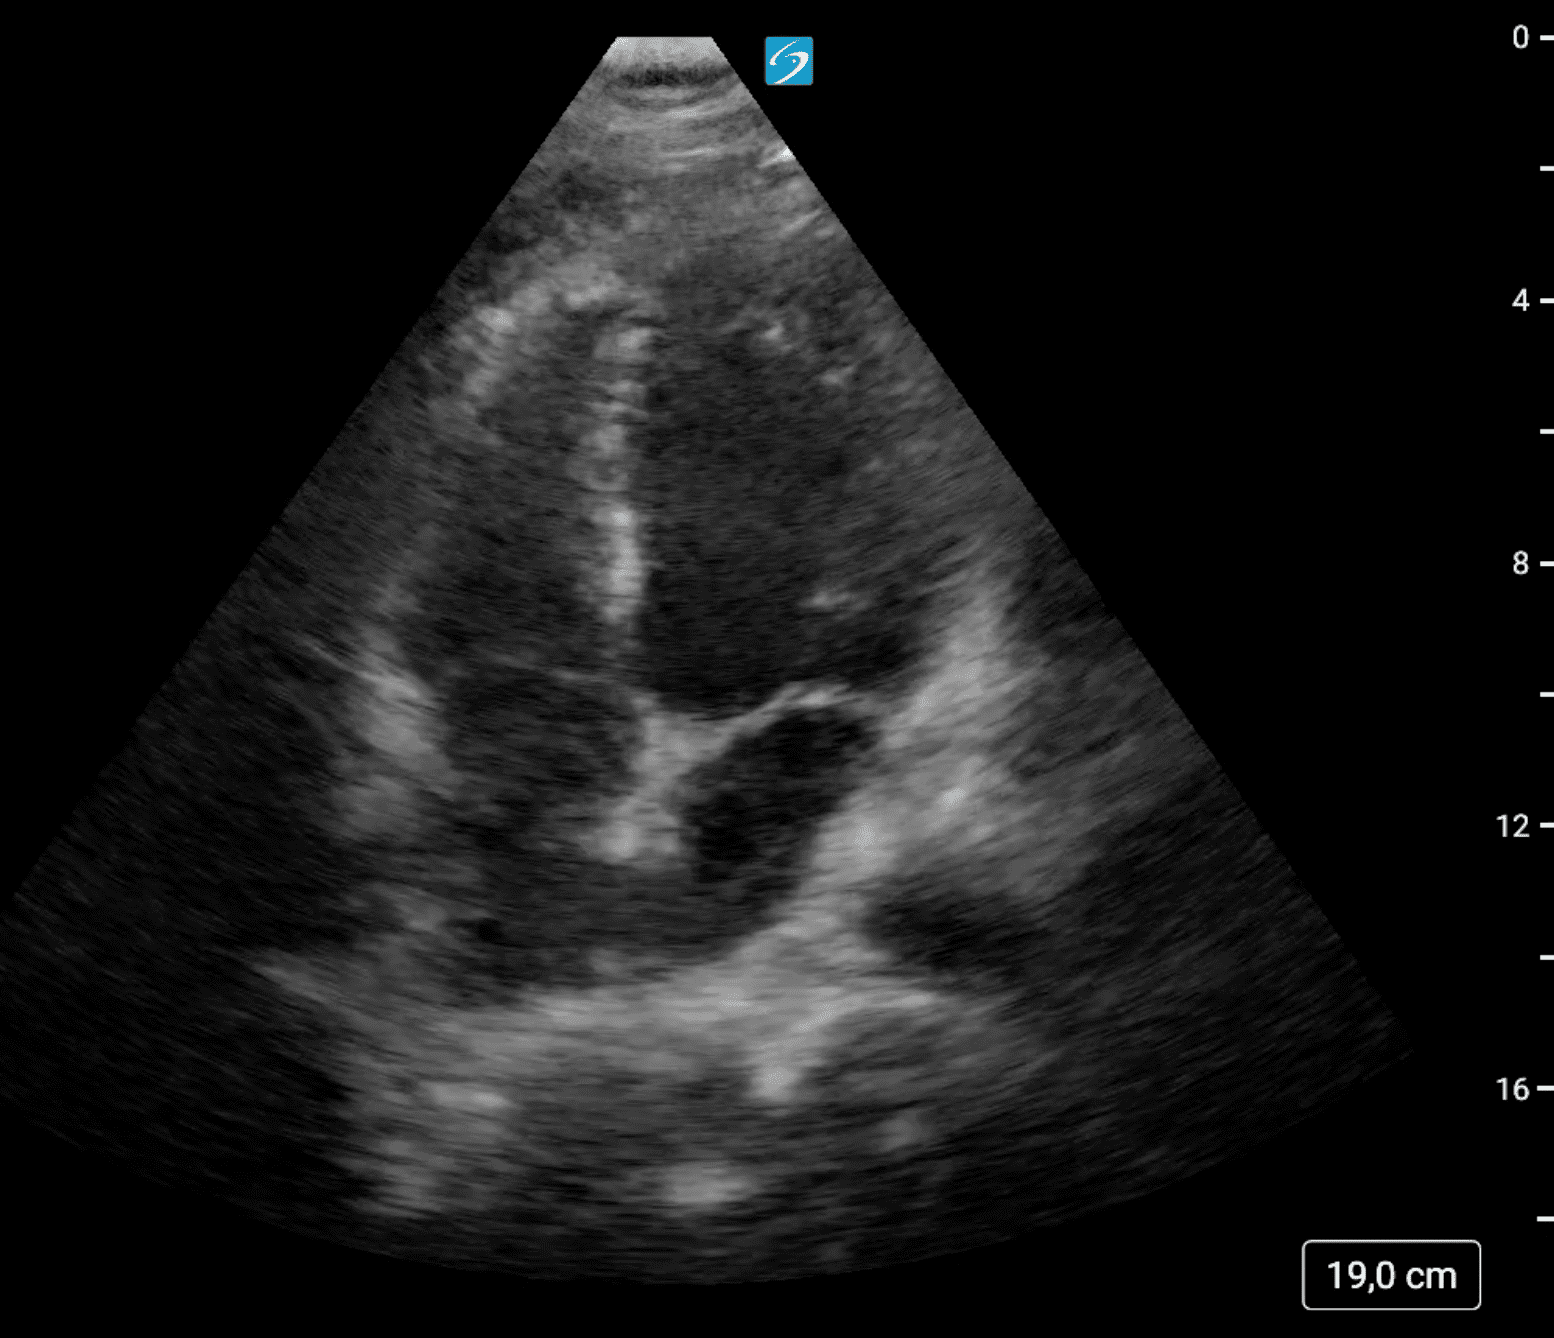

Se localiza ecográficamente la vena femoral común con una imagen hipoecogénica que no colapsa con a la compresión y que se extiende por femoral superficial hasta poplítea. Tras hallazgos, se realiza también una ecografía cardíaca, con un diámetro de visu VD/VI < 1 y con una función cardíaca conservada, con resultado en escala PESI de riesgo bajo.